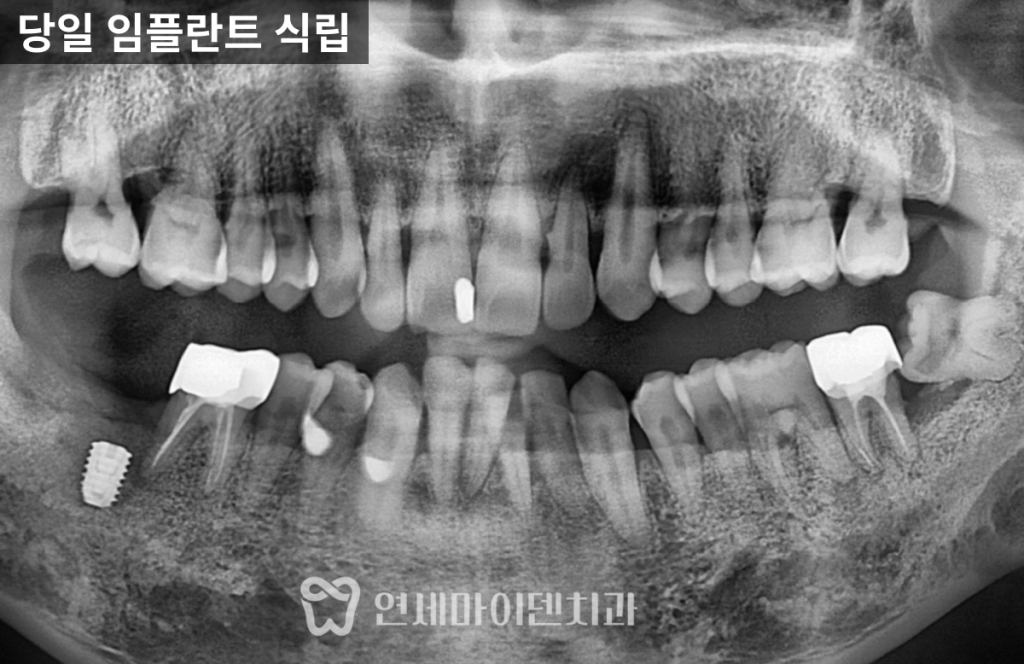

빠른 판단이 필요합니다.치료 전 상태: 뼈가 거의 없는 상황

이번 환자분은

오른쪽 위 어금니는 심하게 흔들리는 상태였고

아래 왼쪽 어금니는 발치 후 오래 방치되었습니다.

CT를 확인해보니

뼈가 거의 남아 있지 않았고,

손으로도 발치가 가능할 정도였습니다.이 상태를 오래 두면

4년 경과: 결과는?

이번 케이스는

4년이 지난 현재까지✔ 임플란트 안정적 유지

✔ 주변 치아 뼈 레벨 유지

✔ 정기 관리 지속임플란트의 수명은